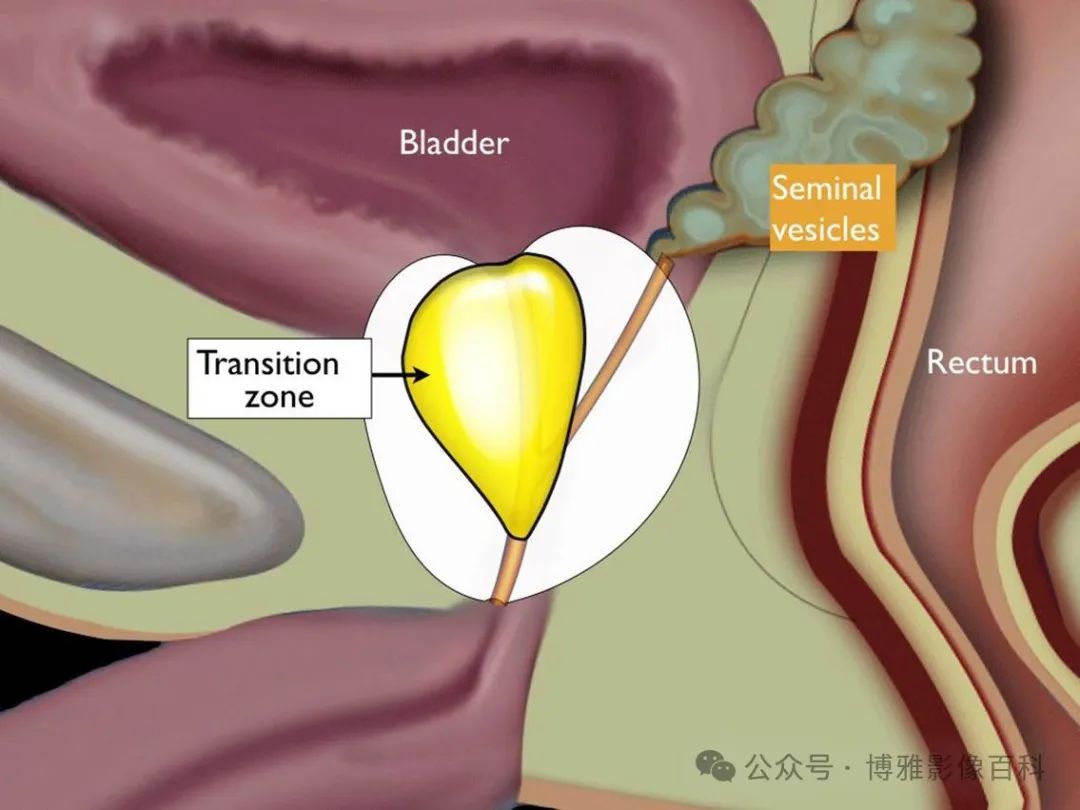

前列腺分区解剖学

25% 的前列腺癌起源于移行带 (TZ)。极少数前列腺癌出现在中央带或前纤维肌基质中。

扇区解剖